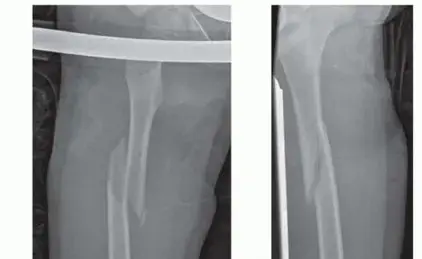

• الأشعة السينية (X-rays): هي الفحص الأساسي والأول لتأكيد وجود الكسر، تحديد موقعه، نوعه، ومدى تفتته. تُؤخذ صور من زوايا متعددة (أمامية وجانبية) لإعطاء صورة واضحة وشاملة للكسر.

هو عبارة عن مسامير معدنية (عادةً من التيتانيوم أو الفولاذ المقاوم للصدأ) ذات قطر صغير ومرونة عالية. تُدخل هذه المسامير من خلال شقين صغيرين (عادةً بالقرب من الركبة) في الطرف القاصي لعظم الفخذ، ثم تُدفع باتجاه الطرف الداني داخل القناة النخاعية للعظم عبر الكسر، لتُشكل قوسًا داخل العظم وتوفر تثبيتًا شبه صلب للكسر. تُساعد مرونة المسامير على توزيع القوى على الكسر، مما يُحفز عملية التئام العظم الطبيعية.

• إدخال المسامير: تُدخل مسامير التيتانيوم المرنة ذات الأقطار المناسبة (عادةً مسمارين) من خلال الشقوق إلى داخل القناة النخاعية لعظم الفخذ. يتم توجيه المسامير بعناية فائقة باستخدام جهاز الأشعة السينية المتنقل (C-arm fluoroscopy) لمراقبة وضعها بدقة وتجنب مراكز النمو.

• اختزال الكسر وتثبيته: تُدفع المسامير عبر خط الكسر، وتُستخدم قوة الدفع والمرونة لتثبيت شظايا العظم في الوضع الصحيح (اختزال الكسر). تُشكل المسامير قوسًا يُوفر الاستقرار للكسر.

• التأكد من التثبيت: بعد إدخال المسامير وتثبيت الكسر، تُؤخذ صور إشعاعية إضافية للتأكد من أن الكسر في محاذاة جيدة وأن المسامير في وضعها الصحيح.